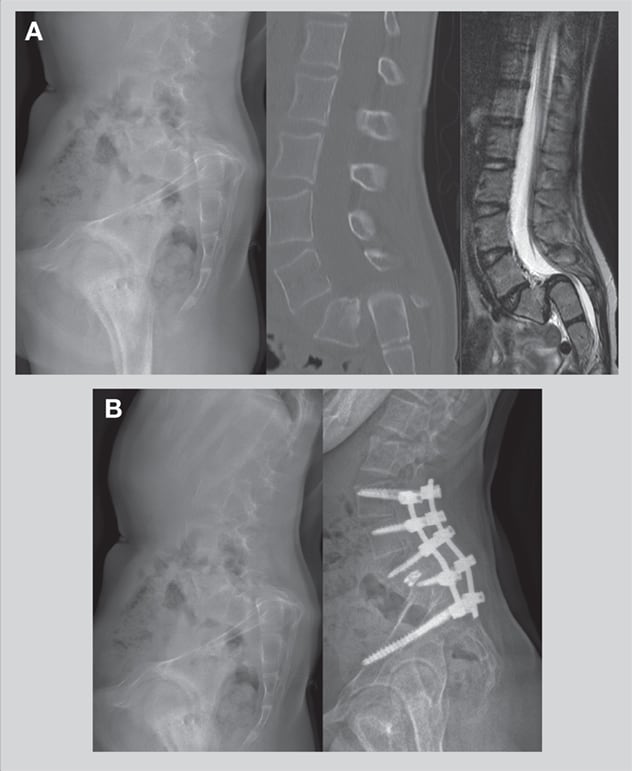

Postoperative X-rays show spinal hardware inserted during a robot-assisted, minimally invasive L4-S1 transforaminal lumbar interbody fusion performed at Mayo Clinic in Jacksonville, Florida. The patient was a 74-year-old man who previously underwent right-sided L4 and L5 foraminotomies for right lower extremity weakness without significant benefit. The minimally invasive fusion greatly improved his leg strength.

The new system's major benefit is greater precision in the placement of hardware during spinal surgery. CT or fluoroscopic imaging before and during surgery help determine the path used by the robot at every level of the spine.